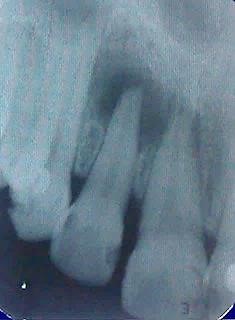

Paciente A.A.G.L., leucoderma, sexo masculino, 55 anos, foi encaminhada para a Clínica de Atenção Básica III da Faculdade de Odontologia de Pernambuco, em Camaragibe, PE, Brasil, para avaliação da necessidade de tratamento endodôntico no dente 12. Na anamnese, não foi relatado qualquer alteração de saúde sistêmica. No exame físico foi verificada ausência de edema e presença de fístula inativa (Figura 1), sem mobilidade, não respondeu ao teste de sensibilidade pulpar, nem à percussão vertical e horizontal.

Figura 1. Radiofrafia inicial comprovando lesão periapical

A partir da radiografia inicial foi observadas extensa radiotransparência periapical bem como, uma área radiopaca na coroa sugestiva de restauração sem invasão da câmara pulpar. O diagnóstico sugestivo foi de abscesso periapical crônico, sendo, assim, indicado o tratamento endodôntico não cirúrgico com a finalidade de obter o reparo da destruição óssea periapical.